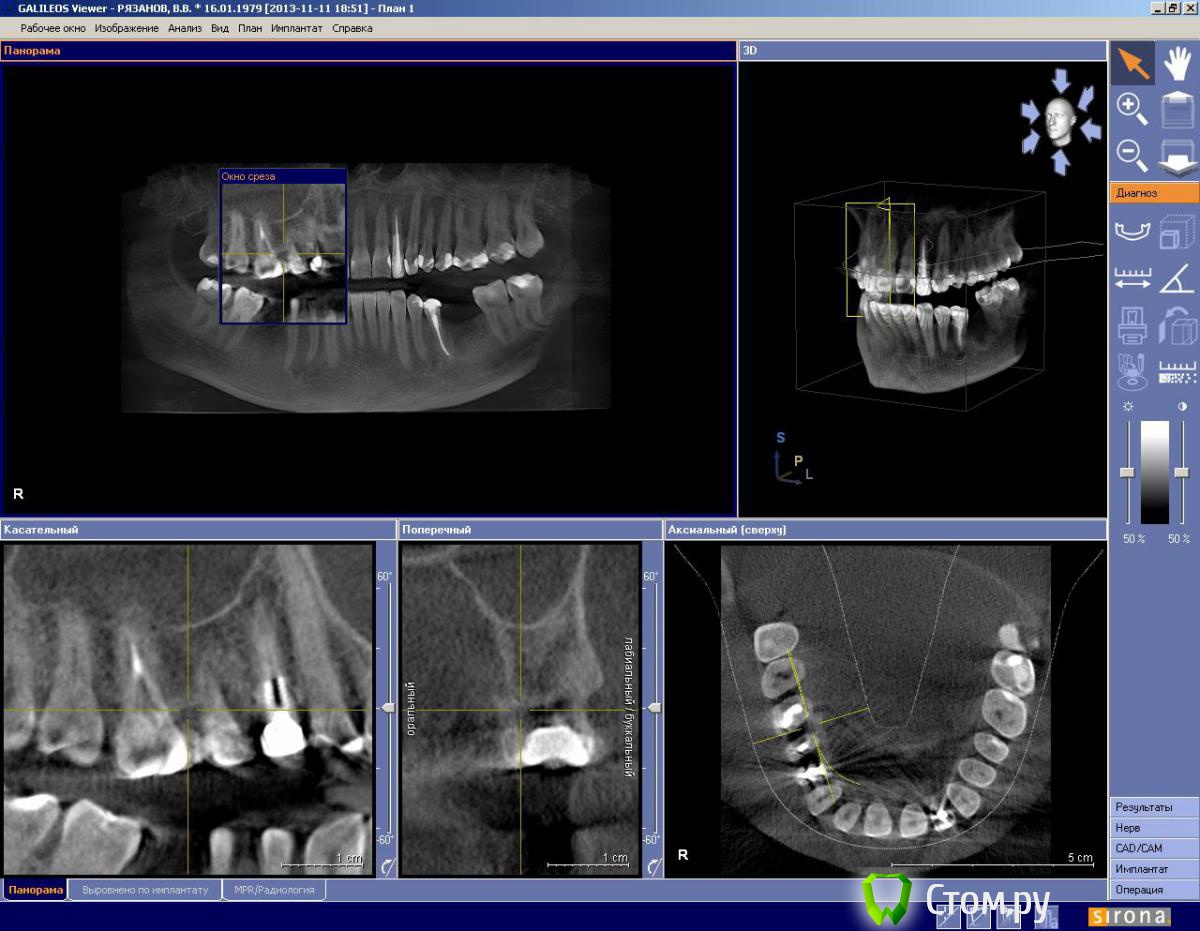

IvanK Опубликовано 14 декабря, 2013 Поделиться Опубликовано 14 декабря, 2013 Для ответа на Ваш вопрос нужны скриншоты других срезов.Или выложите панорамный снимок( оптг) Ссылка на комментарий

Наталия1978 Опубликовано 16 декабря, 2013 Автор Поделиться Опубликовано 16 декабря, 2013 Для ответа на Ваш вопрос нужны скриншоты других срезов.Или выложите панорамный снимок( оптг)Спасибо.)))Могу выложить КТ если устроит. Ссылка на комментарий

IvanK Опубликовано 17 декабря, 2013 Поделиться Опубликовано 17 декабря, 2013 Спасибо.)))Могу выложить КТ если устроит.КТ мало кто может/будет качать.. лучше скриншоты 1 Ссылка на комментарий